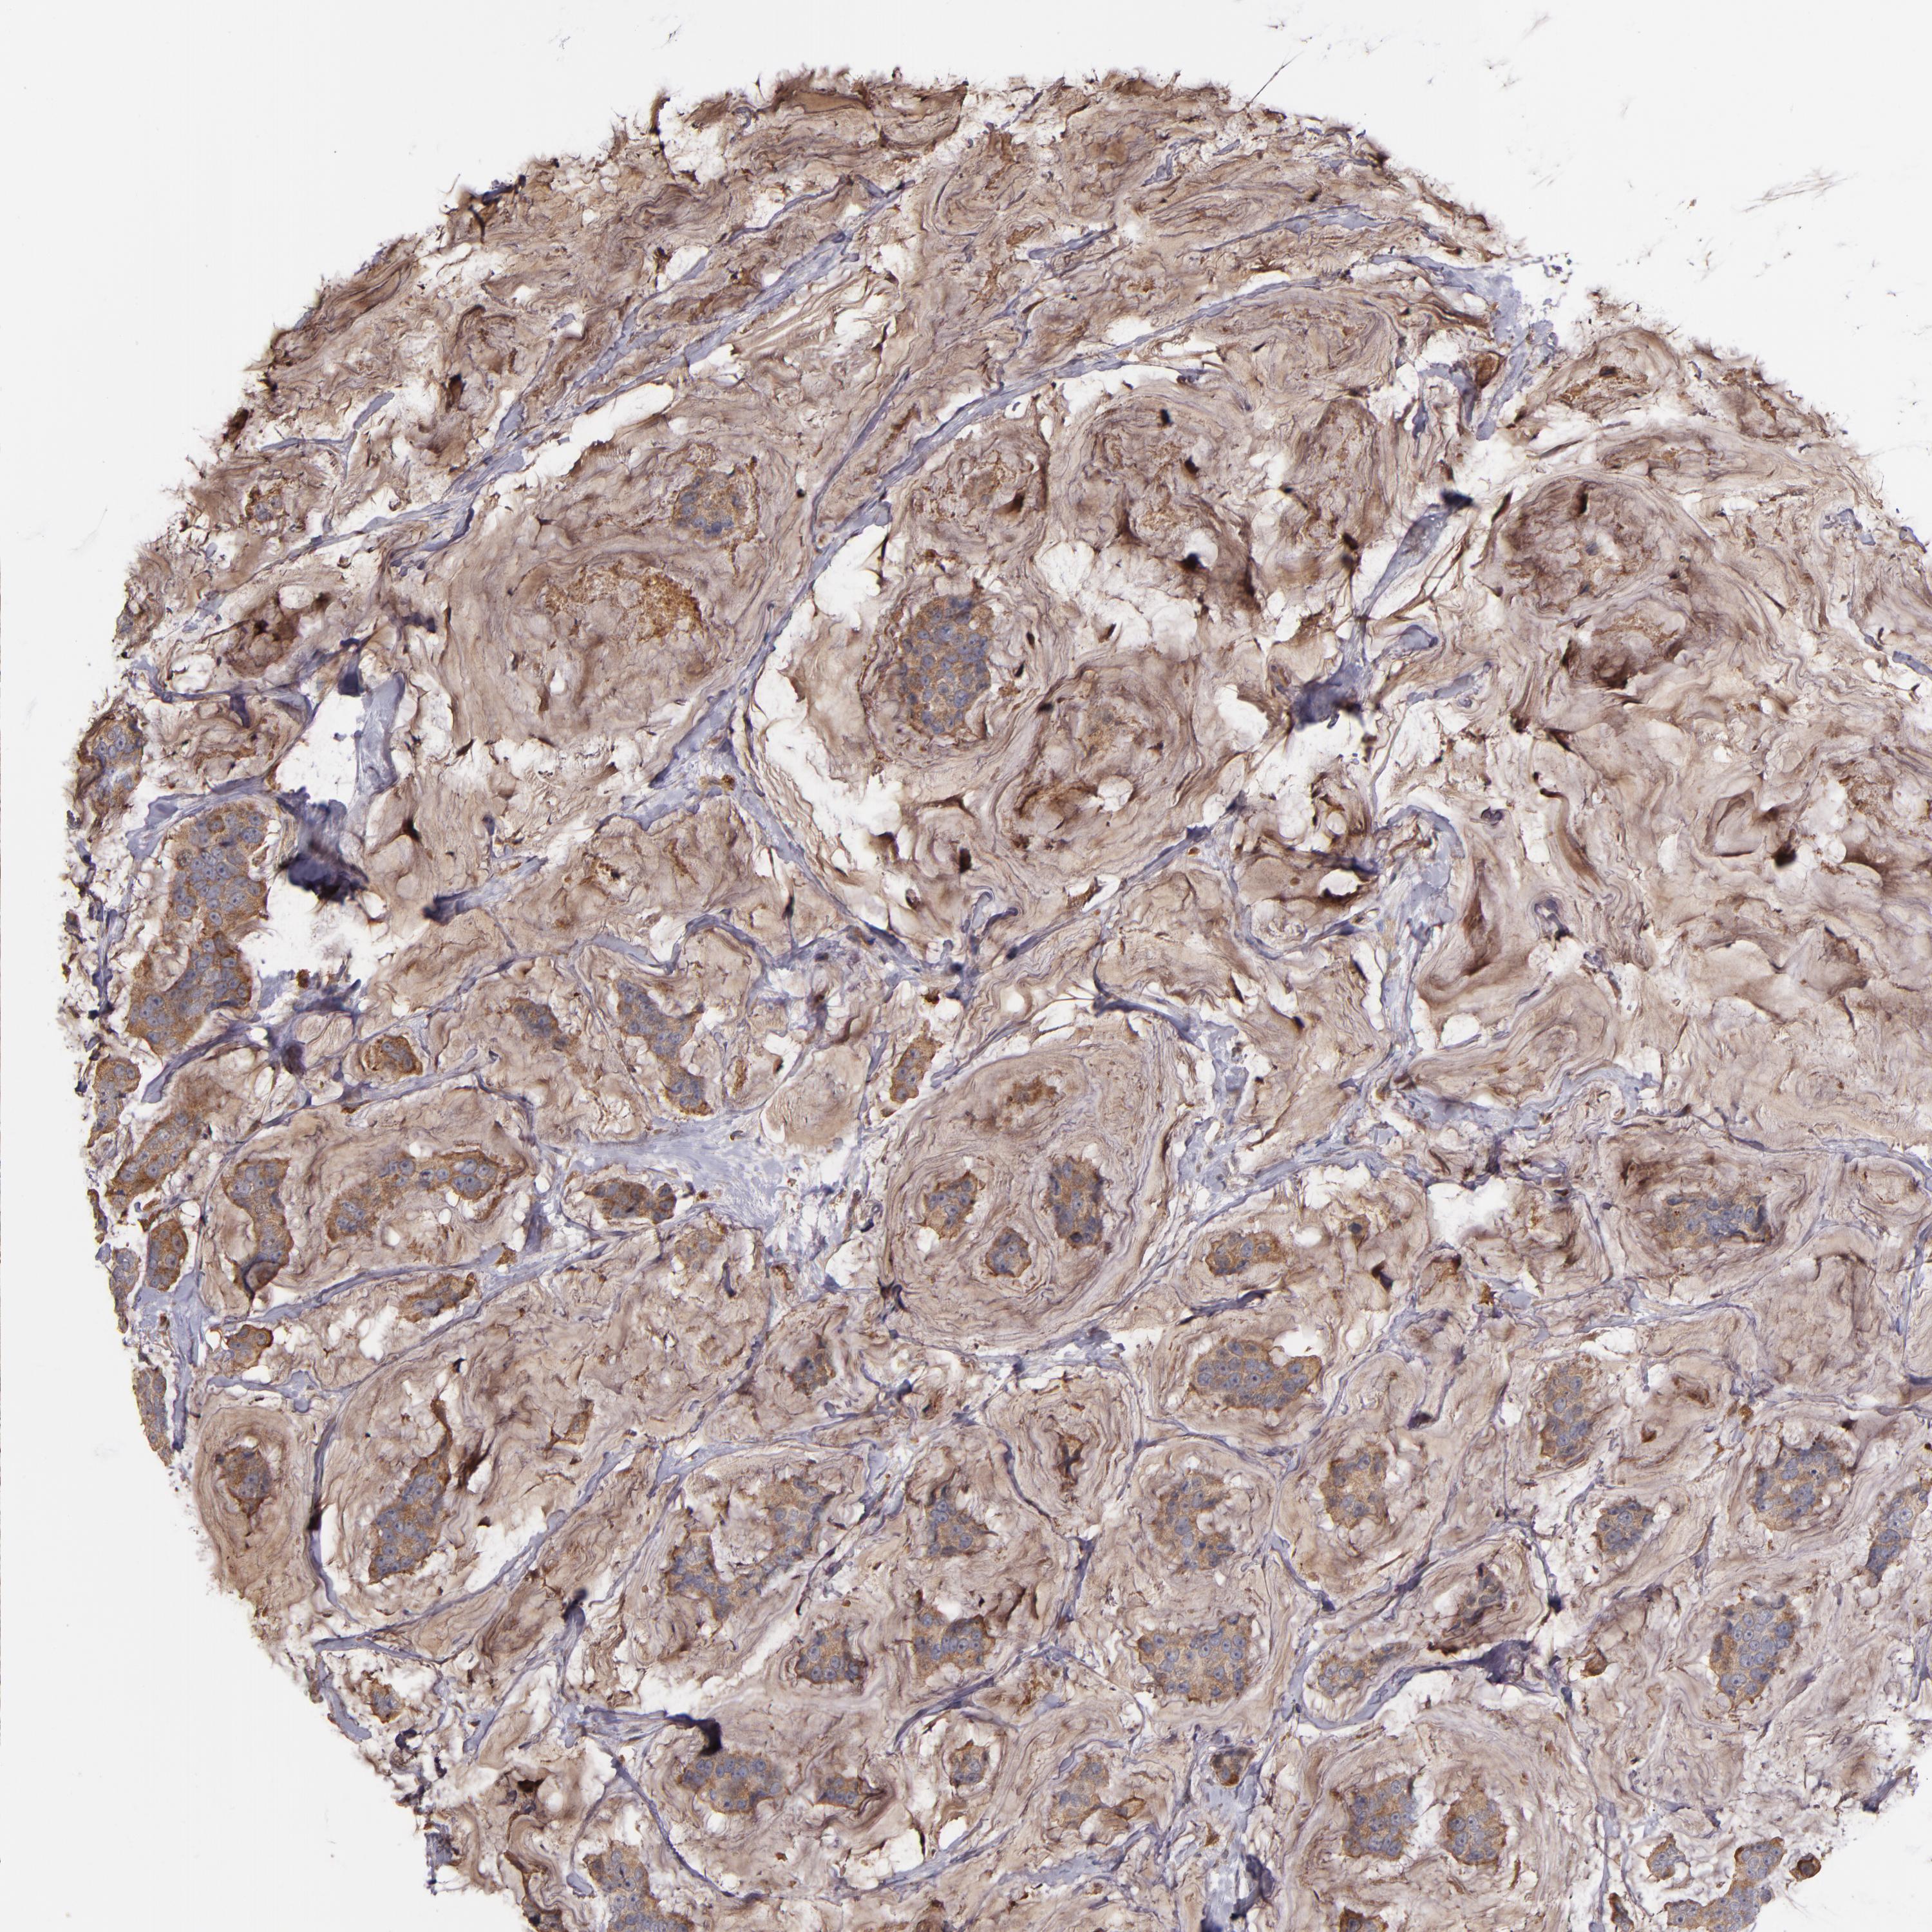

CANCER BREAST CANCER Show tissue menu

BRCA TCGA BRCA VALIDATION PROTEIN EXPRESSION

Breast cancer

Human cancer